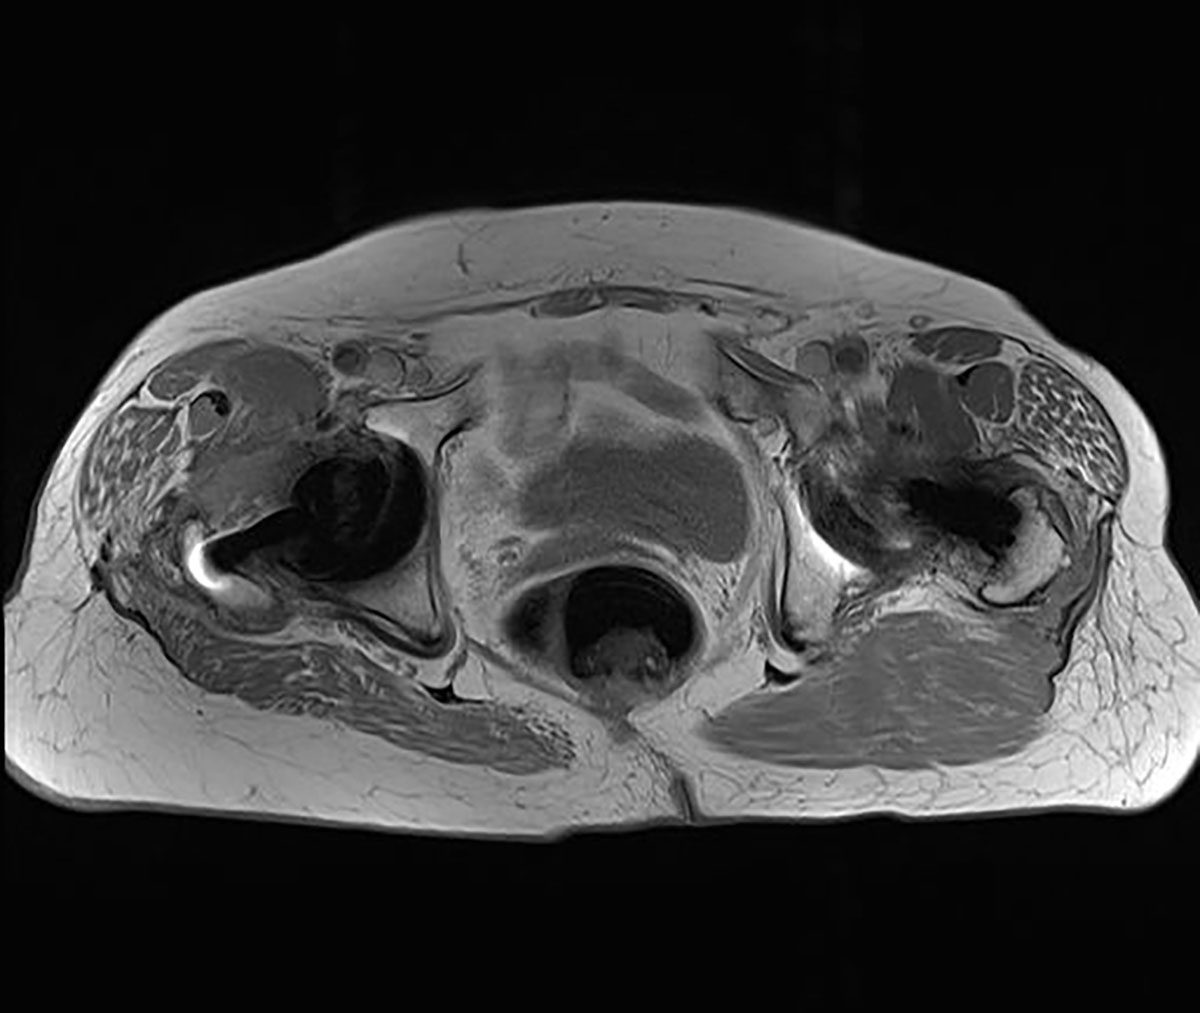

Neben einer typischen Anamnese und klinischen Untersuchung stellt die Bildgebung das entscheidende diagnostische Mittel zum Nachweis einer glutealen Insuffizienz dar. Konventionelle Röntgenbilder (Hüftübersichtsaufnahme a.-p., axiale Projektion des proximalen Femurs, ggf. Faux-Profilaufnahme) dienen zum Ausschluss ossärer Differentialdiagnosen. Bei einliegender Hüft-TEP muss auf mechanische Ursachen wie Lockerung und Komponentenfehlpositionierungen (Drehzentrum der Pfanne, Femur-Offset, Komponentengröße) geachtet werden. Bei nativem Gelenk können peritrochantäre Sehnenansatzverkalkungen oder osteophytäre Ausziehungen als Ausdruck degenerativer Veränderungen erkannt werden. Sonographisch bietet sich die Möglichkeit, ansatznahe Rupturen zu beurteilen, die Sensitivität wird vereinzelt als gut beschrieben. Als Goldstandard gilt die MRT des Beckens. Hierbei gelingt es, durch Wahl geeigneter Sequenzen und Schichtungen Tendinopathien und Rupturen hoch sensitiv nachzuweisen. Bei einliegender Hüft-TEP sind zur genauen Beurteilung der Glutealmuskulatur artefaktreduzierte Sequenzen (z. B. MARS) nötig.